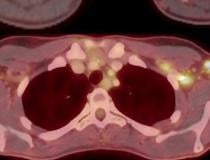

This photo gallery shows the variety of radiological presentations of COVID-19 (SARS-CoV-2) in medical imaging, including computed tomography (CT), radiograph X-rays, ultrasound, echocardiograms and magnetic resonance imaging (MRI). The radiology images show examples of typical COVID pneumonia in the lungs and the numerous complications the virus causes in the body in multiple organs, including the brain, kidneys, heart, abdomen and vascular system.

Ultrasound, especially hand-held ultrasound imaging devices, have become a primary imaging modality for novel coronavirus because of the ease to bag the device and sterilize it after use. CT and mobile X-ray systems are also used as front-line imaging systems for COVID-positive or suspected COVID patients.